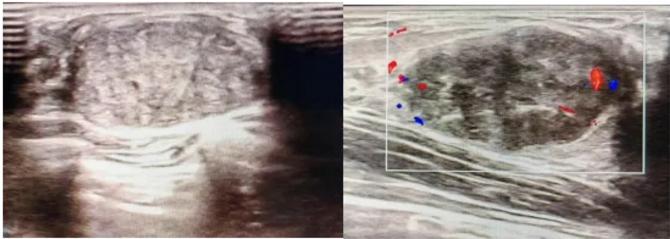

典型表現(xiàn):

橢圓形低回聲團(tuán)塊,包膜完整,內(nèi)部回聲均勻,后方回聲增強(qiáng),周邊無(wú)“蟹足樣”浸潤(rùn)。

血流信號(hào):纖維瘤血流較少,惡性常伴豐富雜亂血流。

形態(tài):良性多呈橢圓形或分葉狀,邊界光滑。

縱橫比: 良性通常<1(橫徑>縱徑) 。